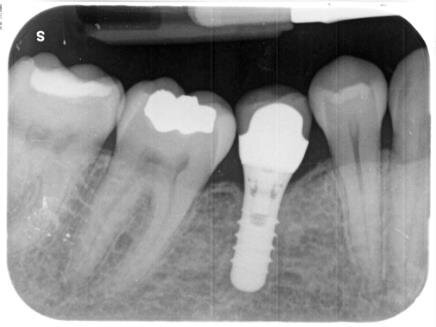

Il trattamento è iniziato a maggio 2018 e si è concluso a novembre 2018, rispettando i tempi e gli obiettivi previsti nel setup iniziale grazie all’ottima collaborazione della paziente e a un’efficace progettazione del caso. Non è stata necessaria alcuna procedura di rifinitura. Dopo circa due mesi dall’inizio della terapia ortodontica, è stato posizionato un impianto in zona 4.6. Si è scelto un impianto tissue level con superficie SLA (Tissue Level RN, Institut Straumann AG, Basel CH) con porzione transmucosa liscia, particolarmente indicato per la sostituzione degli elementi dentari posteriori. Il periodo di guarigione raccomandato per questo tipo di impianti è di 8 settimane.

Fig. 7 - Radiografia post-operatoria a conclusione della riabilitazione protesica dell’impianto in posizione 4.6.